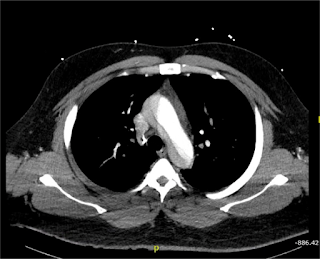

Patient’s initial EKG showed ST elevation in anterior leads, with possible ST depression in inferior leads, and T wave inversion in lateral leads. Given the patient’s clinical presentation and appearance, there was concern for ongoing ischemia. Based on the patient’s history of pain radiating into the abdomen and severe hypertension, there was additional concern for aortic dissection. This led to the cancelation of the catheterization lab activation. Slices of his computed tomography (CT) scan are shown below, revealing a severe type A aortic dissection, dissecting from the coronary arteries to the bilateral iliac arteries. Patient was started on nitroprusside and esmolol infusion and transferred emergently for cardiovascular surgery. He was discharged from the hospital in good condition less than one week later following an uncomplicated post-operative course.